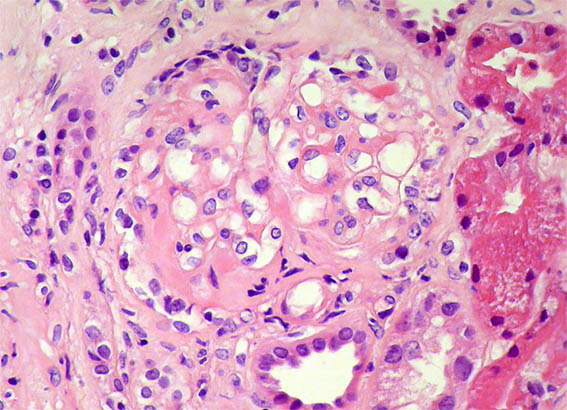

Figura 4. H&E, X400. Otra lesión esclerosante segmentaria.